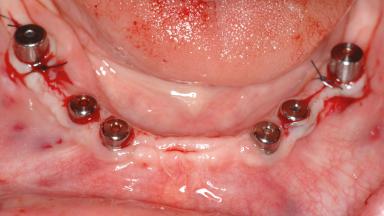

# of Implants 14

Type of Implants Two-Piece

Bone Augmentation Horizontal|Sinus Floor Elevation|Staged|Vertical

Defining Characteristics Fully edentulous upper jaw to be rehabilitated with four or more implants

Modality Fixed hybrid bridge on 5+ implants

Bone Volume Deficient vertically or deficient vertically AND horizontally